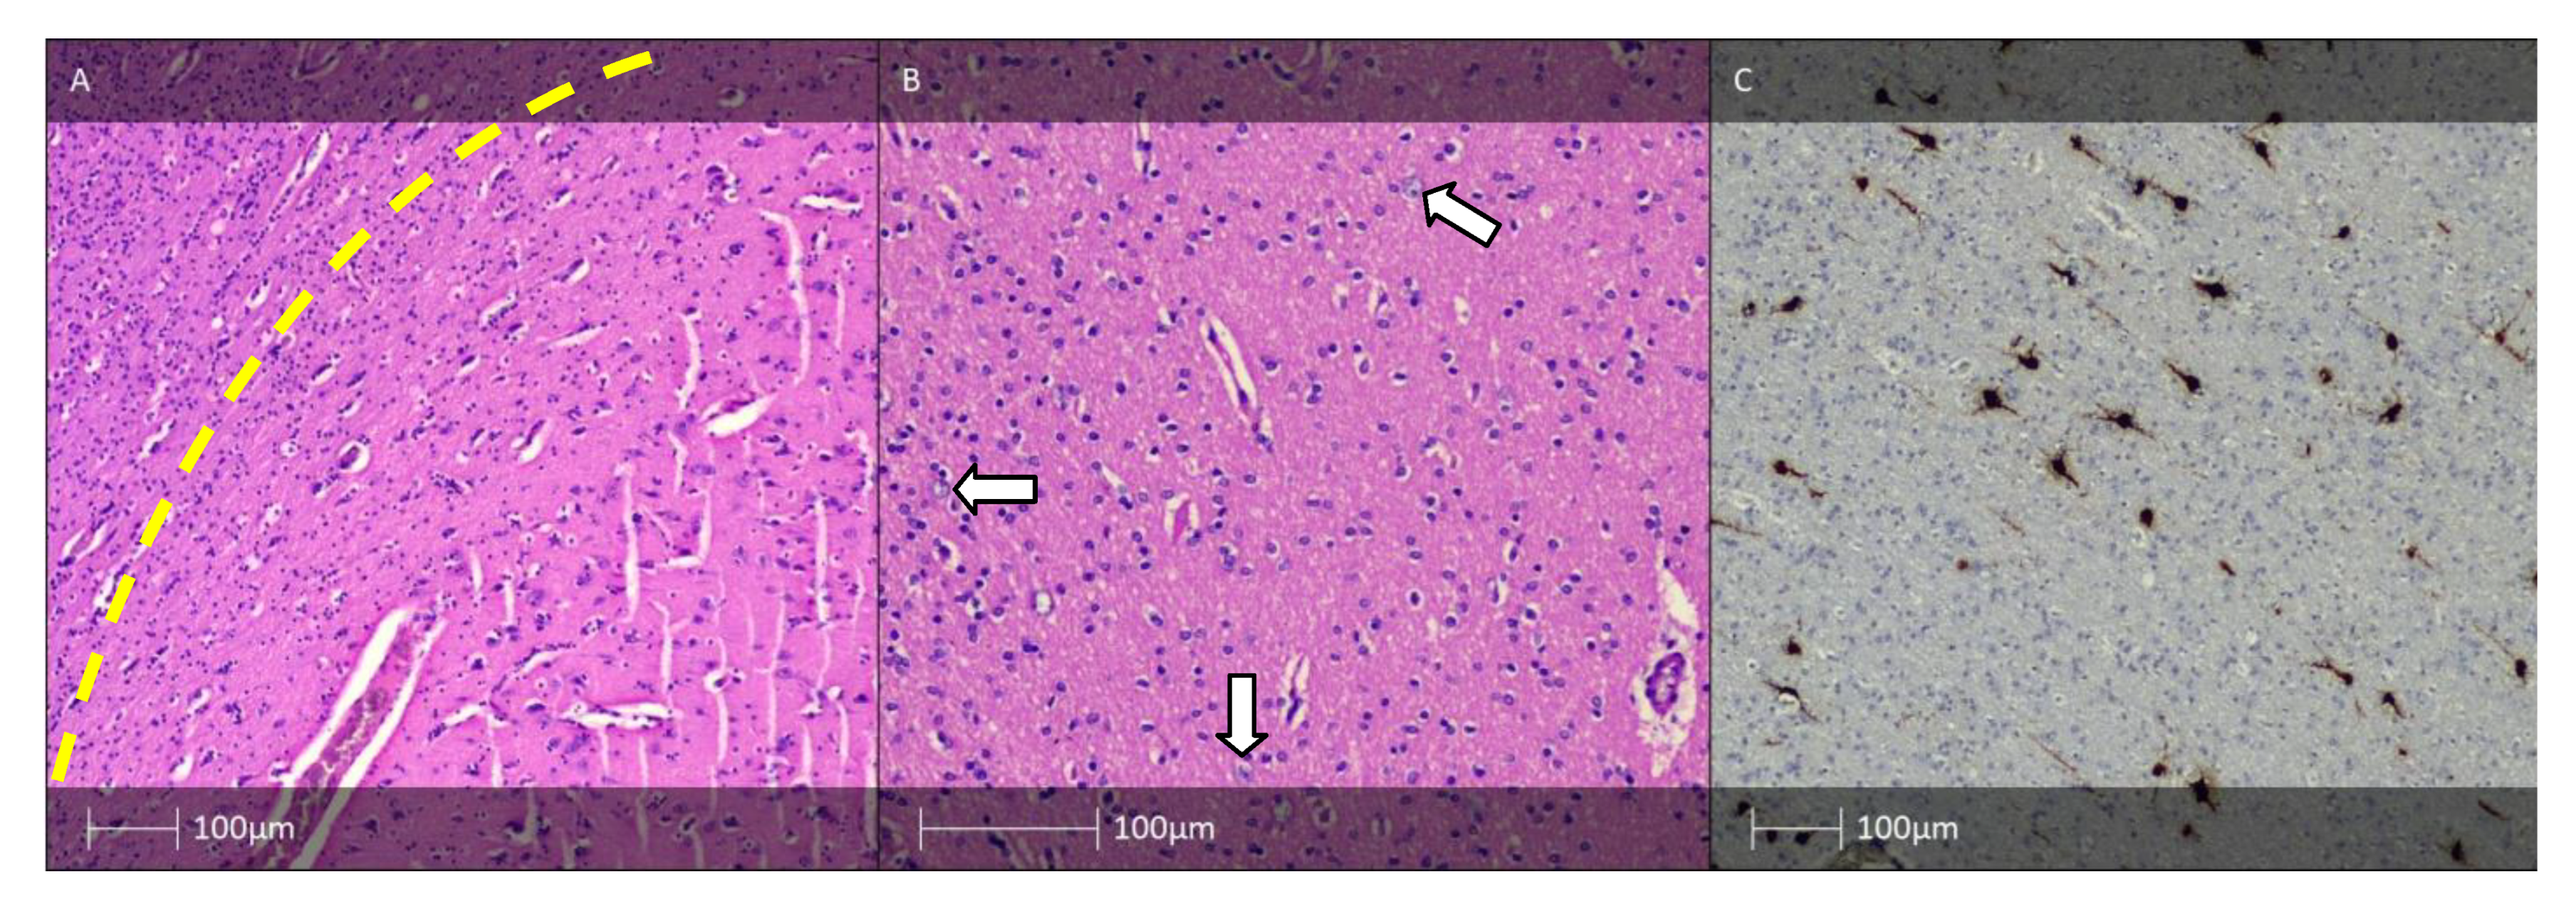

5. Hippocampal Sclerosis and FCD Associated with Hippocampal Sclerosis (FCD IIIa)